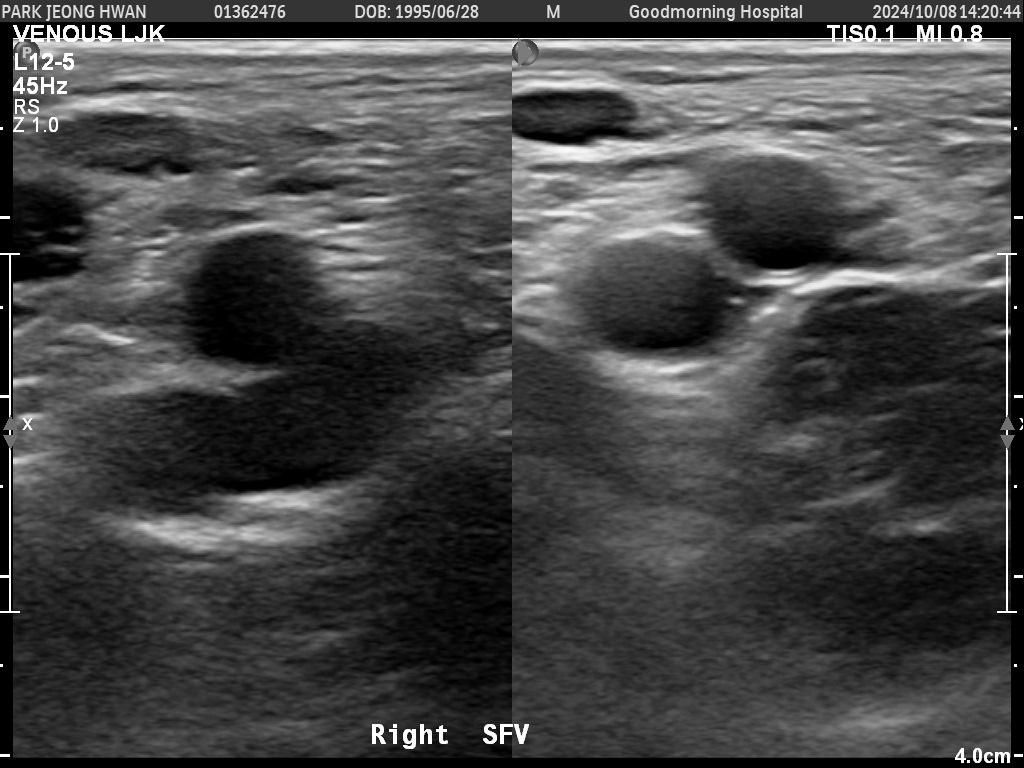

오른쪽 다리만 찍은 거구요. 종아리에서 사타구니까지 부분별로 찍었습니다.......................

• 1번 째 사진

• 2번 째 사진